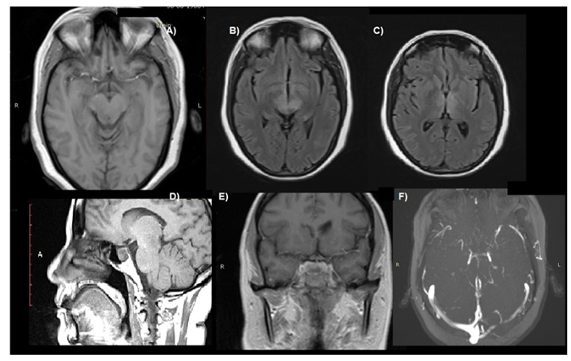

Thoracoscopic Neuroprotective Phrenotomy; A New Surgical Technique for Idio- pathic Incurable Chronic Hiccups